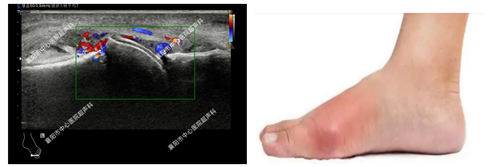

3、类风湿及痛风性关节炎的评估

(图中为痛风患者的第一跖趾关节出现病变)